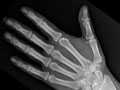

An extremity X-ray is a picture of your hand, wrist, arm, foot, ankle, knee, hip, or leg. It is done to see whether a bone has been fractured or a joint dislocated. It is also used to check for an injury or damage from conditions such as an infection, arthritis, bone growths (tumors), or other bone diseases, such as osteoporosis.

An extremity X-ray is a picture of your hand, wrist, arm, foot, ankle, knee, or leg. It is done to see whether your bone has been fractured or your joint dislocated. It is also used to check for an injury or damage from conditions such as infection, arthritis, bone growths (tumors), or other bone diseases, such as osteoporosis. In an emergency, the doctor can see the initial results of an extremity X-ray in a few minutes. Otherwise, a radiologist usually has the official X-ray report ready the next day.